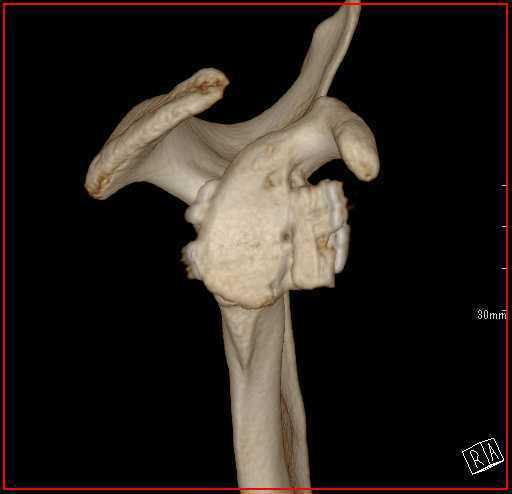

脱臼を繰り返すとどうなるか

脱臼を繰り返すと、前方を支える軟部組織(関節唇、関節包)がさらに損傷していき、最終的には受け皿の骨(肩甲骨)が欠けて小さくなったり、上腕骨の後方に大きな骨欠損が生じたりします。その結果、スポーツ活動はもちろん、日常生活にも大きな影響が出て生活の質(QOL)が著しく低下してしまいます。

特に 若年者や接触スポーツを行う方、骨欠損がある場合は再発リスクが非常に高い ため、早期に正しい治療を受けることが非常に重要です。

関節窩骨欠損がある場合の手術法

AGR(鏡視下バンカート修復術+腸骨移植)

骨盤(腸骨)から骨を採取して、欠損した肩甲骨の関節窩にブロックを用いて移植します。その後、鏡視下バンカート修復術を行います。

鏡視下バンカート修復術+Bristow法

肩甲骨の一部である烏口突起を切り離して、関節窩にスクリューを用いて固定します。その後、鏡視下バンカート修復術を行います。